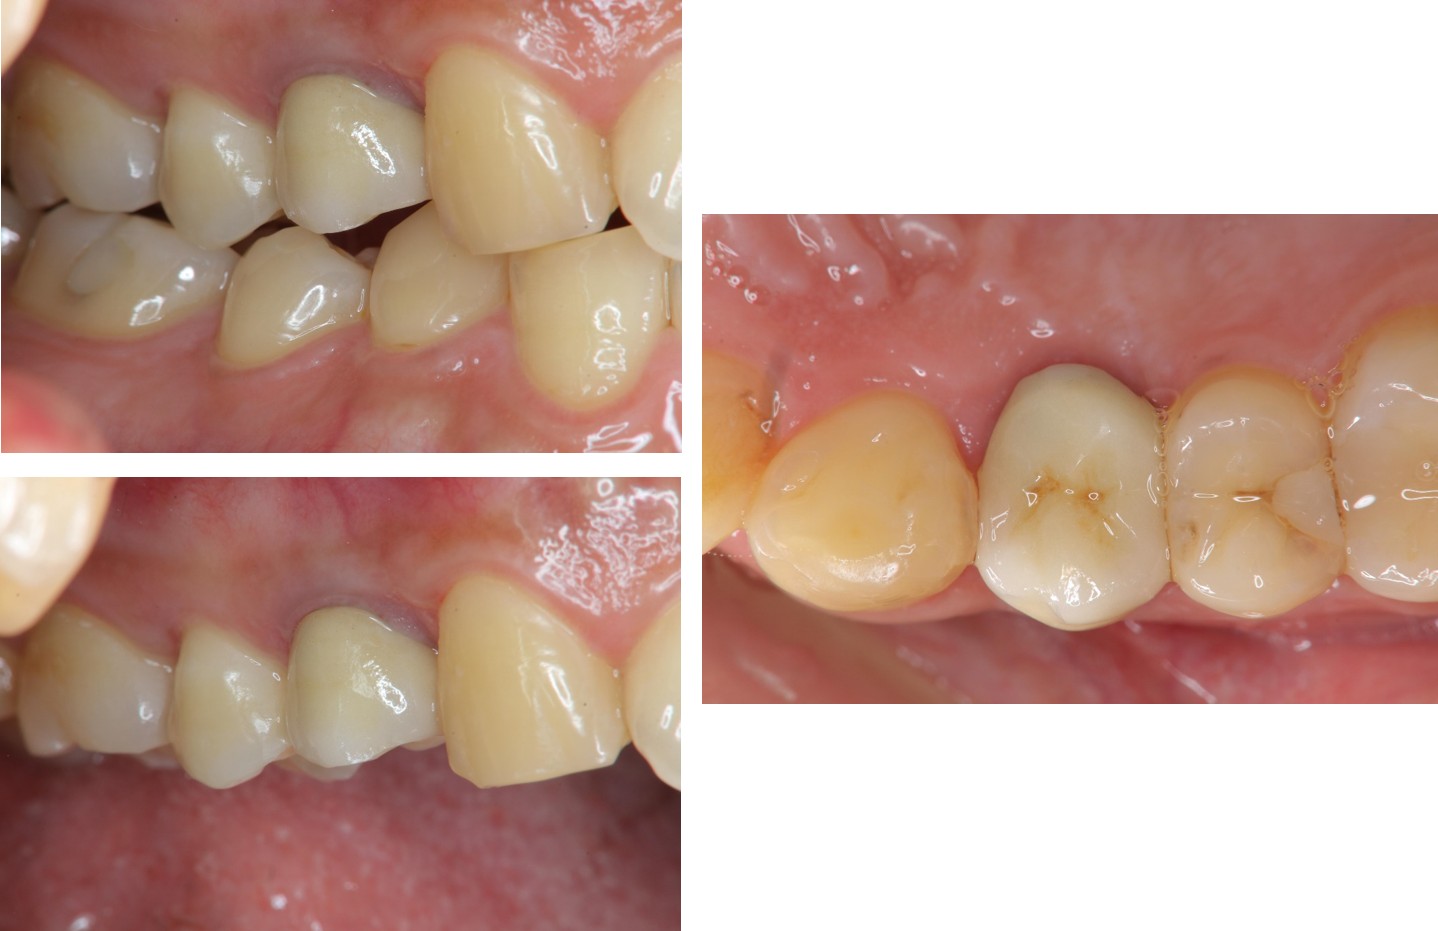

治療前,右上第一小臼齒疼痛

膺復前評估牙齦、牙齒狀態

治療後,咬合良好

術前、術後比較